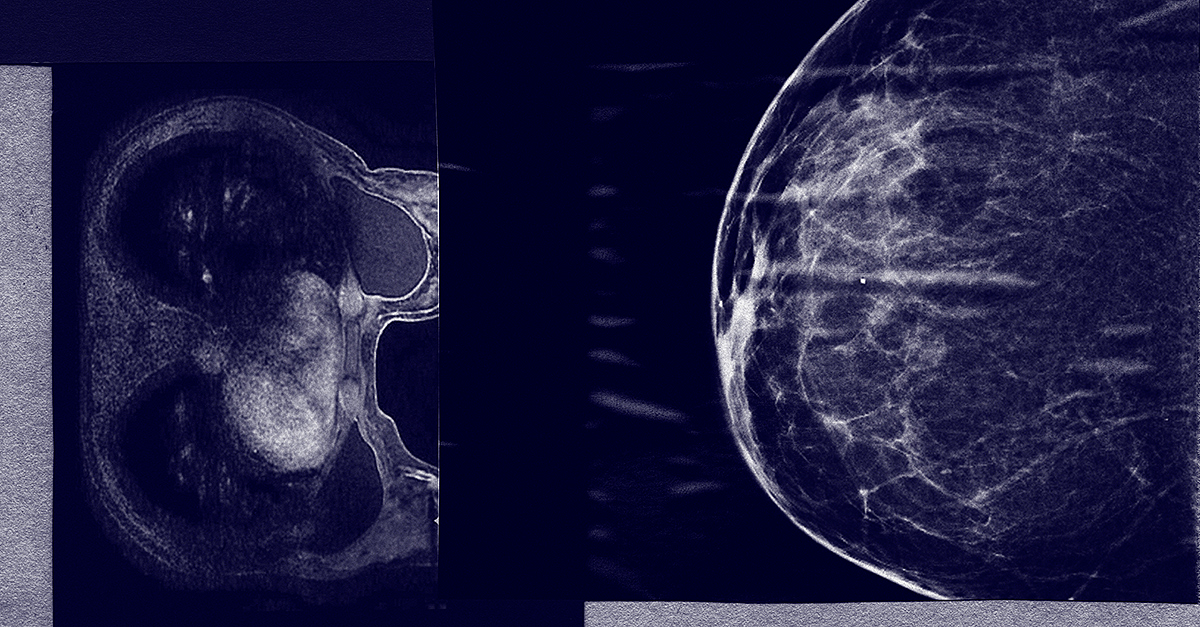

Mammogram or MRI: Which One Should You Choose?

When you get a mammogram, your breast is compressed between two firm surfaces to spread out your breast tissue. The lab technician uses X-rays to capture a black-and-white image on a computer screen. Once your mammogram is complete, a radiologist studies the images to see if there are any signs of cancer. The scan itself usually takes around 10 to 15 minutes.

If you have dense breasts, an MRI may be a better option for detecting cancer. For instance, if you have a family history of breast cancer or are at a higher risk, you may want to ask your doctor about an MRI. A breast MRI uses a dye, gadolinium, put into the person's body to see breast tissue density. During this procedure, you will lie flat on your back as you are moved through a radio imaging tube, which can show a complete resolution of your breasts. Because the MRI screening is so accurate, it often detects everything—even growths that could be benign cysts.